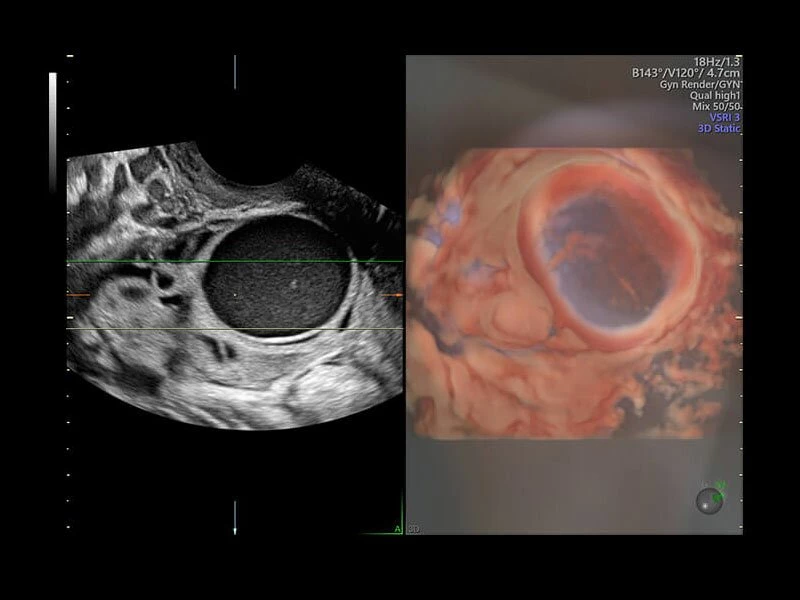

Четкие и подробные изображения

В медицинском учреждении, которое работает в условиях высокой нагрузки, значение имеет каждая минута. У врача нет времени подолгу корректировать параметры настройки, чтобы добиться наилучшей детализации изображения. Инновационная архитектура УЗИ аппарата Voluson E10 избавляет вас от лишних хлопот, — вы сразу получаете безукоризненную картинку. Вам не придется тратить лишнее время и силы: качество визуализации безупречно в любом режиме — от двумерных изображений до новейших 3D/4D технологий.

Современные клинические приложения и высокое качество изображений позволяют использовать Voluson E10 для наблюдения за ходом беременности максимально эффективно. С помощью этого аппарата можно проводить любые исследования, как рутинные, так и комплексные, выявляя проблемы на ранних стадиях и принимая своевременные меры.

Объемное сканирование Voluson — 3D/4D вашей мечты

Объемное УЗИ на Voluson E10 — это не просто потрясающе красивая картинка, это ценный инструмент получения дополнительной информации при обследовании женщин.

Voluson E10 поддерживает инновационные технологии формирования изображений — HDlive Silhouette и HDlive Flow, которые позволяют увидеть мельчайшие детали. Алгоритм SonoRenderlive упрощает рабочий процесс и дает возможность реконструировать изображение поверхностей, определяя область перехода между тканью и жидкостью.

Инновационная технология визуализации HDlive обеспечивает получение реалистических изображений за счет эффекта объемного зрения, повышая достоверность клинической оценки. Теперь режим HDlive дополняют две новые функции:

- Технология HDlive Silhouette — задает разный уровень прозрачности, помогая выявлять контуры внутренних структур и точнее оценивать состояние плода в первом триместре.

- Усовершенствованный режим объемной визуализации с контрастированием (Volume Contrast Imaging, VCI) и опция OmniView

- Повышает контрастное разрешение и улучшает визуализацию области интереса в любой плоскости сечения, даже при исследовании структур неправильной формы.

- SonoRenderlive

- Улучшает объемную визуализацию за счет автоматического определения линии начала реконструкции при изображении поверхностей. При исследовании в режиме 4D функция SonoRenderlive непрерывно обновляет положение исходной линии с учетом движений плода.